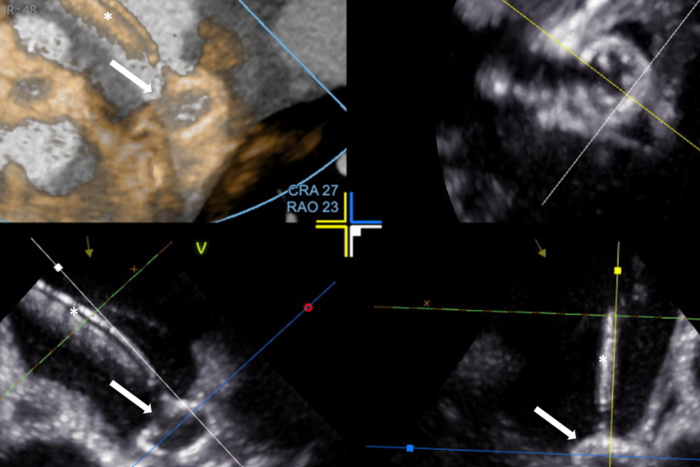

Kwalifikacja do zabiegów prowadzona jest na Oddziale Chorób Strukturalnych Serca, którego koordynatorem jest prof. Marcin Fijałkowski z I Katedry i Kliniki Kardiologii GUMed. Kluczową rolę w planowaniu zabiegów odgrywa echokardiografia przezprzełykowa i tomografia komputerowa serca. Szczegółową analizą obrazów tomografii komputerowej zajmuje się prof. Edyta Szurowska kierująca II Zakładem Radiologii GUMed oraz dr Dorota Kulawiak-Gałąska z Zakładu Radiologii naszego Uniwersytetu.

Zespół zabiegowy tworzą dr Piotr Drewla, dr Rafał Gałąska i dr Maksymilian Mielczarek z I Kliniki Kardiologii kierowanej przez prof. Marcina Gruchałę. Pacjenci w trakcie zabiegu prowadzeni są przez zespół specjalistów z Katedry i Kliniki Anestezjologii i Intensywnej Terapii GUMed kierowanej przez prof. Radosława Owczuka.